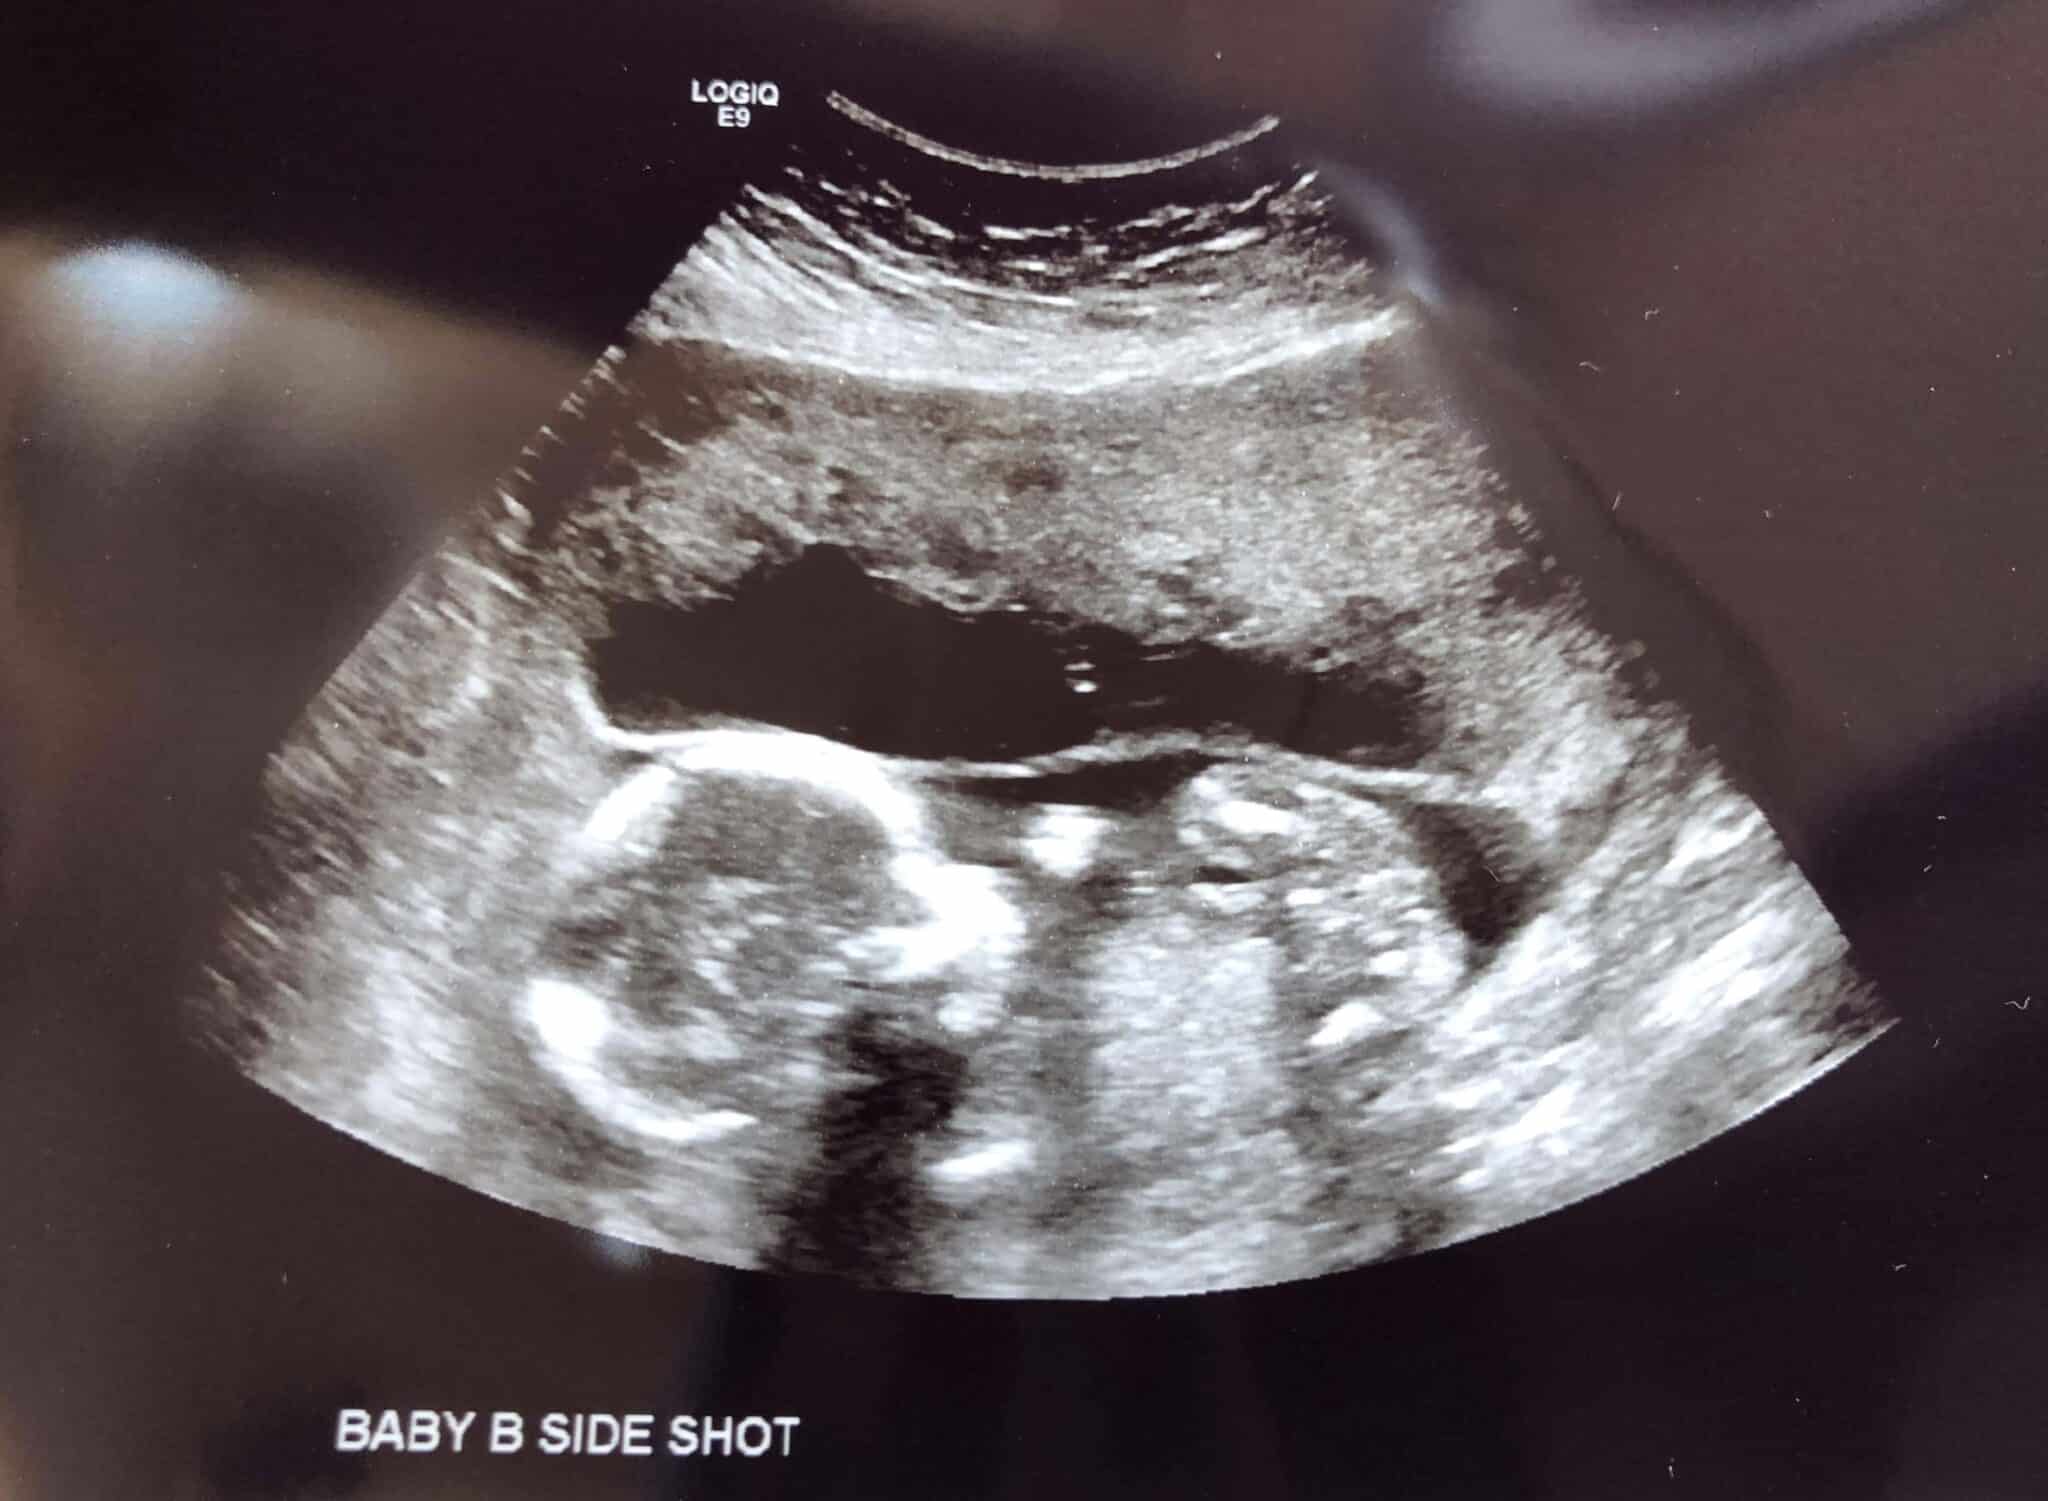

Ultrasound Photos at 19 Weeks Pregnant With Twins